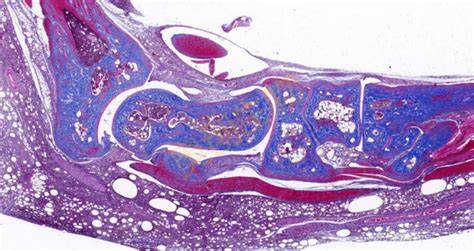

Masson染色是一种用于显示组织中纤维成分的特殊染色方法,主要用于区分胶原纤维和肌纤维,在病理学和组织学研究中有广泛的应用。**一、染色原理**1. 试剂作用 - **酸性复红**:它是一种酸性染料,能够将细胞质、肌纤维等染成红色。在染色过程中,酸性复红与肌纤维中的碱性蛋白结合,使肌纤维呈现出红

400-6863-882 立即咨询Masson染色是一种用于显示组织中纤维成分的特殊染色方法,主要用于区分胶原纤维和肌纤维,在病理学和组织学研究中有广泛的应用。

**四、结果观察与分析**

1. 细胞核

- 经过Weigert铁苏木精染液染色后,细胞核呈现黑色。可以观察细胞核的大小、形状、位置以及核内结构(如核仁),这有助于判断细胞的类型和状态。

2. 肌纤维

- 被酸性复红染色后呈红色,通过观察肌纤维的分布、走向和形态,可以了解肌肉组织的结构和功能。例如,在心肌组织中,心肌纤维呈分支状,相互连接成网状;在平滑肌组织中,肌纤维呈长梭形,排列较为规则。

3. 胶原纤维

- 被苯胺蓝染色后呈蓝色。可以观察胶原纤维在组织中的分布和含量,这对于研究组织的纤维化程度、创伤修复等过程具有重要意义。例如,在肝脏纤维化的组织中,会出现大量蓝色的胶原纤维增生。